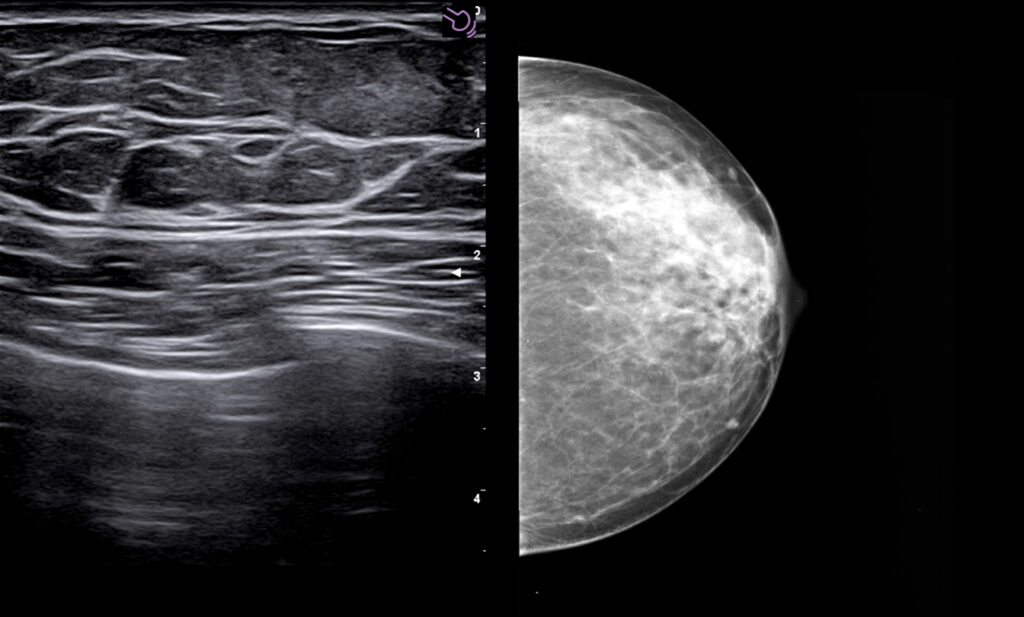

MyLab X90 er Esaote´s nye premiummodell og kommer i 2 spesialversjoner: MSK/Rauma og Brystdiagnostikk. Ultralydapparatet representerer et helt nytt kapittel og standard innen premium ultralyd.

Du ser strukturer tydeligere og mer detaljert enn tidligere. Ultrahøy «framerate» for dynamiske undersøkelser. En super sensitiv og stabil fargedoppler gir en dopplersensitivitet man ikke finner maken til, kombinert med markedets høyeste frekvenser på 25 Mhz. Den nye lineærproben med 4-25Mhz oppløsning, vil bli din nye favoritt. Gir fremragende og markedsledende bildekvalitet på helt overfladiske skanninger, samtidig med premium bildekvalitet ned til 2.5-3.0 cm. Dette er helt enestående for MyLab X90.

Kliniske bilder.